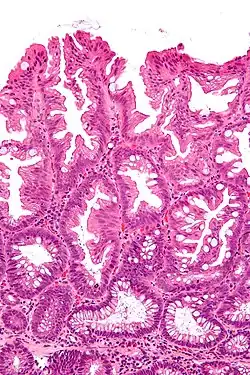

| Hyperplastic polyp seen under microscopy with H&E stain | |